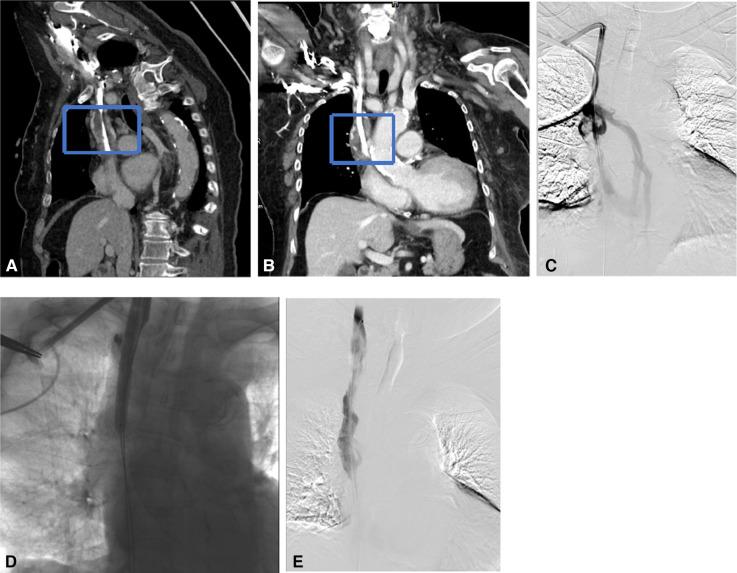

The aim of this study was to evaluate the causes of the dysfunctional tunneled cuffed catheters (TCCs) using multi-spiral computed tomography venography (MSCTV), and to analyze the outcomes of endovascular salvage techniques.

MSCTV showed a range of abnormalities in the hemodialysis (HD) patients, including central venous occlusion ( = 4), fibrin sheath formation ( = 3), malposition of the catheter tips ( = 4), central venous perforation ( = 1), thrombus formation ( = 12), regular catheter exchange without determined lesions ( = 3). Interventional catheter salvage procedures were performed, such as catheter exchange, balloon disruption of a fibrin sheath, angioplasty for central vein stenosis, and stent deployment. The technical success rate for catheter insertions was 100%, and no procedure-related severe complications were observed. The 30-day catheter patency for all assessable catheters was 85.2%.

MSCTV显示血液透析(HD)患者存在一系列异常情况,包括中心静脉闭塞(=4例)、纤维蛋白鞘形成(=3例)、导管尖端位置异常(=4例)、中心静脉穿孔(=1例)、血栓形成(=12例)、无明确病变的常规导管更换(=3例)。实施了介入性导管挽救程序,如导管更换、纤维蛋白鞘球囊破坏、中心静脉狭窄血管成形术和支架置入术。导管插入的技术成功率为100%,未观察到与操作相关的严重并发症。所有可评估导管的30天导管通畅率为85.2%。